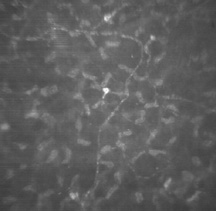

The corneal epithelium is the anterior-most cell layer of the cornea (Fig. 1). It is typically several cell layers thick, consisting of the apical cell squamous layer, the multilayered, polygonal-shaped wing cells beneath the apical layer, and the posterior-most layer of basal cells (Fig. 2). The wing cell layer is two or three cells thick in the central cornea, but tends to be four to five cells thick in the periphery. In total, the epithelium is approximately 50 μm thick in the central human cornea.

Fig. 1. Full-thickness view of the normal human cornea. From top: epithelium, Bowman's layer (arrow), stroma, Descemet's membrane (arrow), and endothelium (hematoxylin-eosin stain, 80×). (Courtesy of Drs. Rodrigues, Waring, Hackett, and Donohoo.)